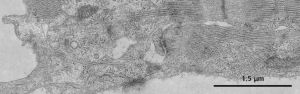

除紅細胞外,內質網或多或少地見於所有各種細胞.內質網為由生物膜構成的互相通連的片層隙狀或小管狀系統,膜片間的隙狀空間稱為池,通常與細胞外隙和細胞漿基質之間不直接相通.

這種細胞內的膜性管道系統一方面構成細胞內物質運輸的通路,另一方面為細胞內各種各樣的酶反應提供廣闊的反應面積.內質網與高爾基體及核膜相連續.

(一)粗面內質網

在病理狀態下,粗面內質網(rER)可發生量和形態的改變.在蛋白質合成及分泌活性高的細胞(如漿細胞,胰腺腺泡細胞,肝細胞等)以及細胞再生和病毒感染時,粗面內質網增多.

粗面內質網的含量高低也常反映腫瘤細胞的蛋白質合成功能的狀態,並在一定程度上反映了腫瘤細胞的分化程度.如惡性程度較高的骨肉瘤細胞中,粗面內質網十分發達.

當細胞受損時,粗面內質網上的核蛋白體往往脫落於胞漿內,粗面內質網的蛋白合成乃下降或消失;當損傷恢復時,其蛋白合成也隨之恢復.

在由各種原因引起的細胞變性和壞死過程中,粗面內質網的池一般出現擴張,較輕的和局限性的擴張只有在電鏡下才能窺見,重度擴張時則在光學顯微鏡下可表現為空泡形成,電鏡下有時可見其中含有中等電子密度的絮狀物.

在較強的擴張時,粗面內質網同時互相離散,膜上的顆粒呈不同程度的脫失.進而內質網本身可斷裂成大小不等的片段和大小泡.這些改變大多見於細胞水腫時,故病變不僅見於內質網,也同時累及Golgi器,線粒體和胞漿基質,有時甚至還累及溶酶體.